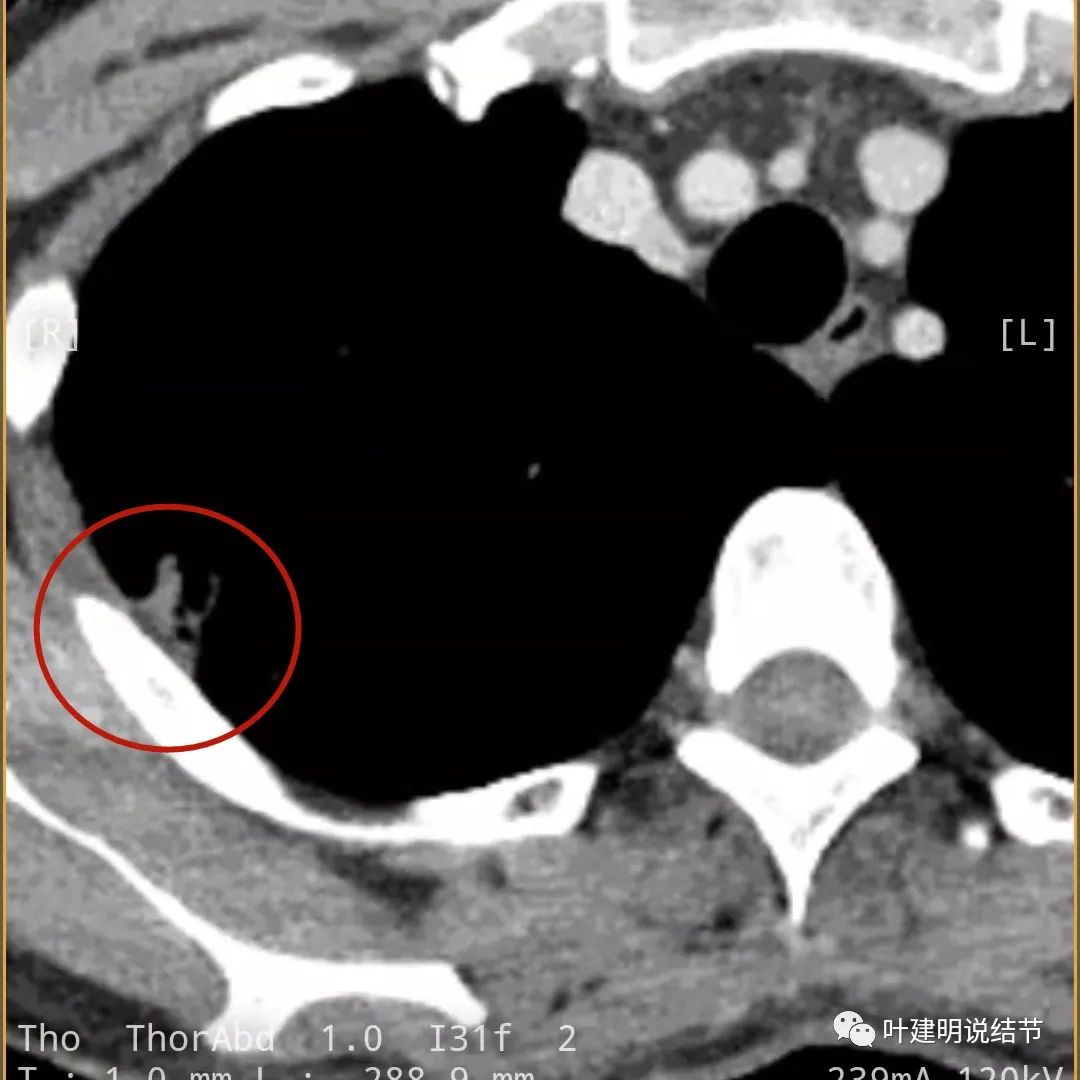

蓝色箭头所指处居然有低密度影,难道是坏死?因为比肌肉密度低,也无强化,况且主病灶的中间也有个低密度的小点状

病灶有明显强化(说明炎性可能性大,如果恶性这样强化,血供丰富,应该倍增速度更快。蓝色箭头示胸膜处低于软组织密度的区域;桔色箭头示病灶边缘平直缺乏膨胀性;黄色箭头示中间的空腔

邻近胸膜处的增厚密度低于肌肉组织,病灶强化明显且均匀

此层也见明显的低密度区域(天蓝色箭头)

胸膜处明显增厚伴低密度区域

天蓝色箭头示病灶低密度区,考虑坏死可能性大,桔色箭头示边缘凹陷无膨胀性

上图示空洞偏心,而且红色箭头所指处与空腔似乎是整合,而非囊壁生长增厚。天蓝色箭头示近胸膜处的低密度区域,考虑坏死成分,囊壁的邻近部分也是极低密度区域,也可能是干酪样坏死区